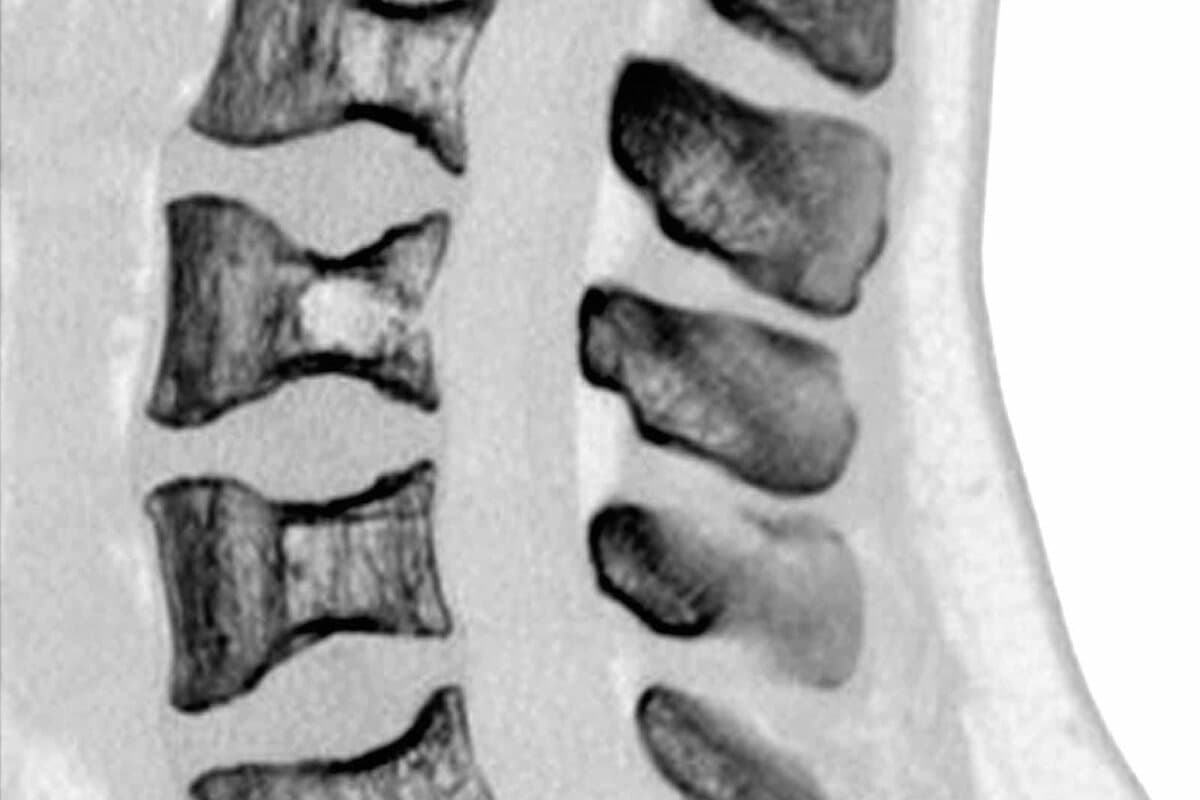

Typischerweise sind tiefere Strukturen wie Knochen, Gelenke, Bänder und Muskeln betroffen. Am häufigsten klagen Betroffene über Schmerzen im Rücken, welche mitunter in die Beine ausstrahlen. Die Intensität reicht von leicht bis sehr schwer.